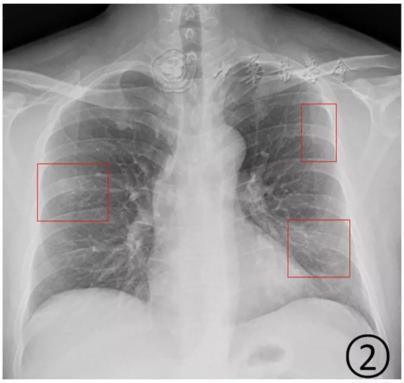

按照国家卫健委发布的新型冠状病毒肺炎试行第六版诊疗方案之中的临床分型,新冠肺炎分为轻型、普通型、重型及危重型。在患者的肺部CT中,轻型者没有比较明显的肺炎改变;普通型者以肺部出现局限性斑片状或很多节段性片状“病灶”为主(图②);重型者双肺可出现较多的白色小斑片“病灶”,部分融合成大片状“病灶”(图③);危重型者会有“白肺”表现(图④)。

▲从上到下依次为普通型、重型及危重型新冠肺炎患者的肺部CT表现(图片来自网络)